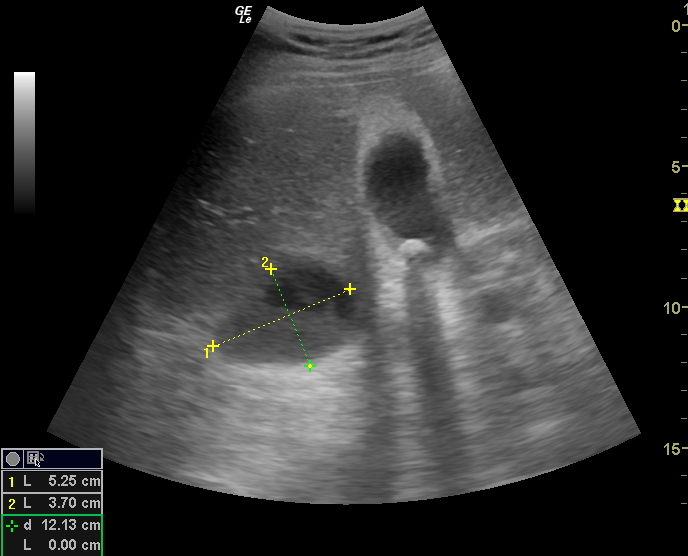

Ecografía de vesícula, dolor en hipocondrio derecho. YouTube Timpanismo En Hipocondrio Derecho El paciente se coloca en posición de decúbito supino, se deben percutir los cuatro cuadrantes del abdomen. En ocasiones, al profundizar la mano sobre el hipocondrio derecho se percibe el desplazamiento del líquido y luego se choca con el hígado. El hipocondrio derecho es el área de proyección del hígado, la vesícula biliar y el duodeno, mientras que en el. Timpanismo En Hipocondrio Derecho.